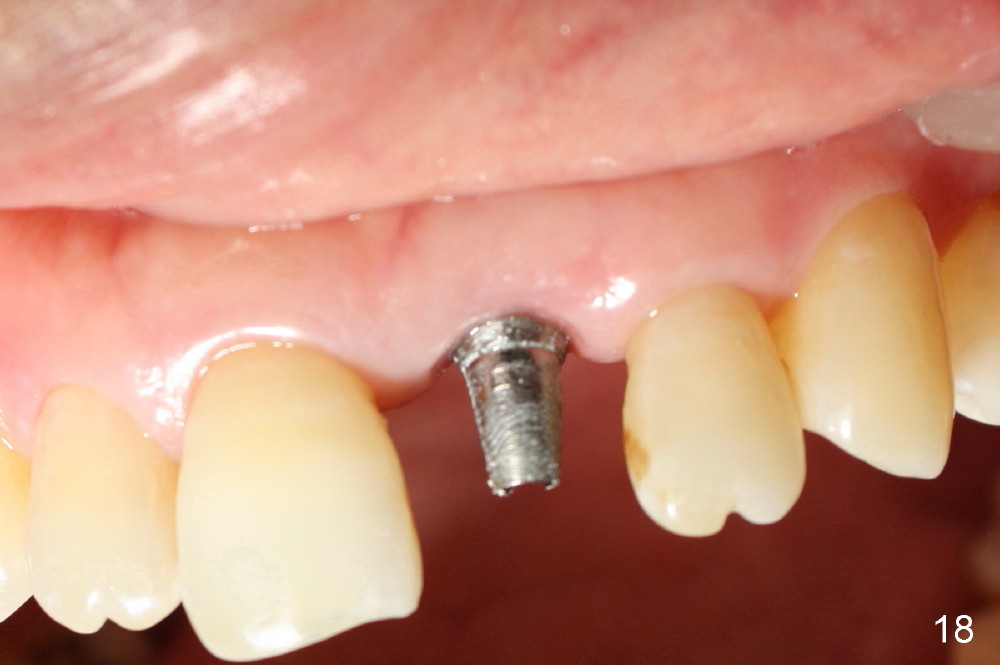

A 60-year-old lady had an abscess mesial to #9 six years ago (Fig.1,2 <), treated as a perio lesion by laser (Fig.3) and osseous surgery without bone graft (Fig.6, followed by CT exam revealing semi-circumferential bone loss (Fig.4,5). When the perio treatment failed, attention was paid to endo aspect (Fig.7-9). In fact the pulp was found to be vital when access to root canal therapy was made. As expected, the treatment failed again. The palatal fistula persisted. The infection was suspected to be a source of remote immediate implant site (#30). The tooth #9 was extracted. It appears that there is a semilunar crack line in the linguomesial root (Fig.12). When the socket healed 2 weeks post extraction (Fig.10), the #30 buccal defect was debrided with bone graft. There was no bone resorption 4 weeks post extraction (Fig.11); a 4.5x17 mm implant was placed (Fig.13-15). An immediate provisional was fabricated (Fig.16-18). Fig.19,20 were taken 3 months post implantation and 7 months post cementation, respectively. Dense bone forms around the implant coronally 4 years 5 months post cementation (Fig.21), while the gingiva is healthy palatally (Fig.22) and buccally (Fig.23).